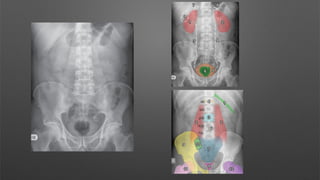

Inclusion

The entire anatomy should be included from the

hemi diaphragms to the symphysis pubis.

‐

• The superior aspect of the liver (1) and spleen (2)

should be included at the top of the radiograph.

• The lateral abdominal walls (3) should be seen

on either side of the radiograph.

• The pubic symphysis (4) should be clearly

visualised at the bottom of the radiograph.

This is a supine AP abdominal radiograph.

The pubic symphysis is included on this radiograph,

however the hemi diaphragms are not visualised. Ideally I

would like to see both hemi diaphragms”

A: “There is no evidence of free gas.”

B: “The bowel gas pattern is within normal limits.”

C: “There is no abnormal calcification.”

D: “There is no fracture or bony abnormality.”

E: “There is no evidence of previous surgery, medical

devices or any foreign body.” “

Impression

Normal abdominal radiograph.”

Inclusion The entire anatomyshould be included from the hemi diaphragms to the symphysis pubis. ‐ • The superior aspect of the liver (1) and spleen (2) should be included at the top of the radiograph. • The lateral abdominal walls (3) should be seen on either side of the radiograph. • The pubic symphysis (4) should be clearly visualised at the bottom of the radiograph.